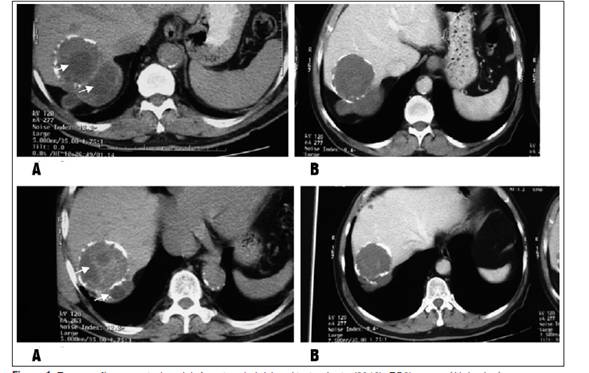

En la TAC de 2015 no se observaron cambios en los quistes en segmento VII, tanto en forma como en tamaño, presentando discreto aumento de las calcificaciones de la pared quística. En cuanto a su contenido, este es más homogéneo y no se visualizan las estructuras internas (vesículas hijas) observadas en estudio imagenológico anterior al tratamiento médico (Figura 1).

Figura 1 Tomografía computada axial. A: antes de iniciar el tratamiento (2013), EC3b con múltiples imágenes compatibles a vesículas hijas en el interior del quiste (flechas). B: (2015) desaparición de los elementos activos y disminución del tamaño quístico al año del tratamiento médico con ABZ, pasando a un estadio inactivo EC3a